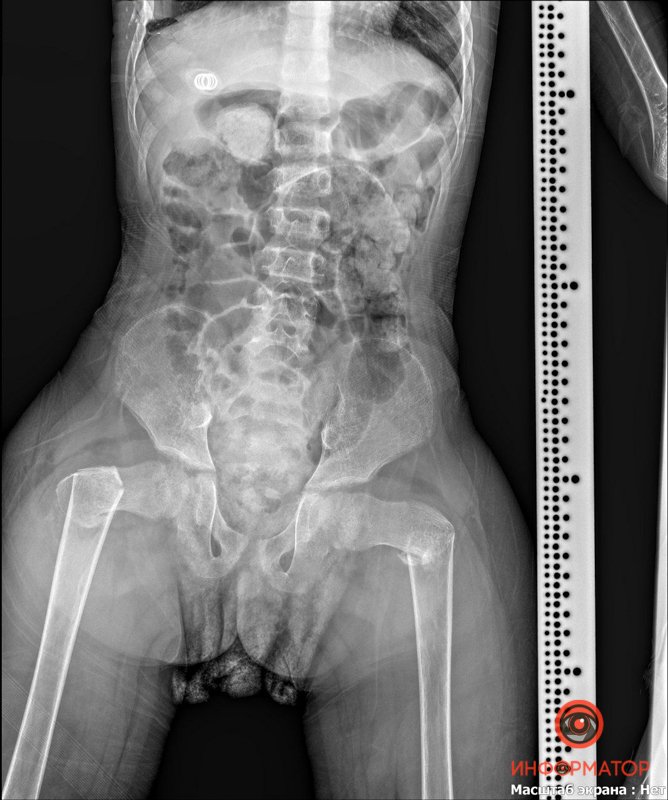

"9 мая к нам доставили мальчика с задержкой в развитии из Никополя. У ребенка случился эпилептический приступ, когда он сидел в "позе лотоса". Как следствие - сломал 2 шейки бедренной кости. Его прооперировали в пятницу по современной методике (открытая репозиция, остеосинтез LCP- пластиной) - сразу выполнено лечение двух бедер. Мальчик уже в палате, без гипсовых повязок, во вторник поедет домой", - рассказал Дмитрий Ершов.

Врач добавил, что обычно такие повреждения лечатся длительным скелетным вытяжением, после чего 2-3 месяца пациент должен пребывать в гипсовой повязке. Малыш же получил современное хирургическое лечение, после которого ему понадобится лишь реабилитация для возвращения способности к ходьбе. Случай такого лечения - крайне редкий, в мировой литературе есть лишь несколько подобных примеров, отмечает врач.